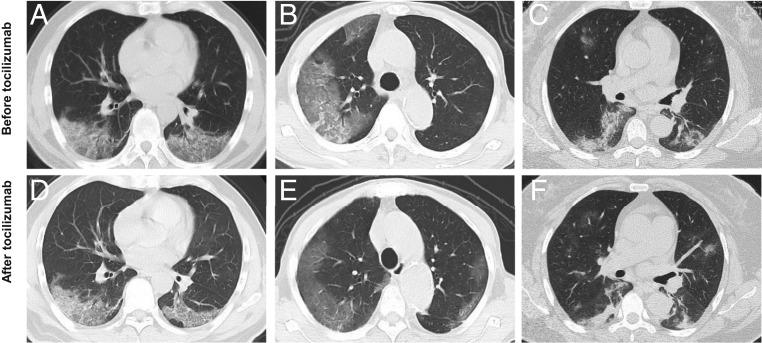

After analyzing the immune characteristics of patients with severe coronavirus disease 2019 (COVID-19), we have identified that pathogenic T cells and inflammatory monocytes with large amount of interleukin 6 secreting may incite the inflammatory storm, which may potentially be curbed through monoclonal antibody that targets the IL-6 pathways. Here, we aimed to assess the efficacy of tocilizumab in severe patients with COVID-19 and seek a therapeutic strategy. The patients diagnosed as severe or critical COVID-19 in The First Affiliated Hospital of University of Science and Technology of China (Anhui Provincial Hospital) and Anhui Fuyang Second People's Hospital were given tocilizumab in addition to routine therapy between 5 and 14 February 2020. The changes of clinical manifestations, computerized tomography (CT) scan image, and laboratory examinations were retrospectively analyzed. Fever returned to normal on the first day, and other symptoms improved remarkably within a few days. Within 5 d after tocilizumab, 15 of the 20 patients (75.0%) had lowered their oxygen intake, and 1 patient needed no oxygen therapy. CT scans manifested that the lung lesion opacity absorbed in 19 patients (90.5%). The percentage of lymphocytes in peripheral blood, which decreased in 85.0% of patients (17/20) before treatment (mean, 15.52 ± 8.89%), returned to normal in 52.6% of patients (10/19) on the fifth day after treatment. Abnormally elevated C-reactive protein decreased significantly in 84.2% of patients (16/19). No obvious adverse reactions were observed. All patients have been discharged on average 15.1 d after giving tocilizumab. Preliminary data show that tocilizumab, which improved the clinical outcome immediately in severe and critical COVID-19 patients, is an effective treatment to reduce mortality.

在分析了严重新型冠状病毒病 2019(COVID-19)患者的免疫特征后,我们发现具有大量分泌白细胞介素 6 的致病性 T 细胞和炎症性单核细胞可能会引发炎症风暴,而针对白细胞介素 6 途径的单克隆抗体可能会抑制这种炎症风暴。在这里,我们旨在评估托珠单抗在 COVID-19 重症患者中的疗效,并寻求一种治疗策略。在 2020 年 2 月 5 日至 14 日期间,在中国科学技术大学第一附属医院(安徽省医院)和安徽阜阳第二人民医院,除常规治疗外,将托珠单抗用于诊断为严重或危急 COVID-19 的患者。回顾性分析了临床表现、计算机断层扫描(CT)图像和实验室检查的变化。发热于第 1 天恢复正常,其他症状在几天内明显改善。托珠单抗治疗后 5 天内,20 例患者中有 15 例(75.0%)降低了吸氧需求,1 例患者无需吸氧治疗。CT 扫描显示 19 例患者(90.5%)肺部病变的不透明度吸收。外周血淋巴细胞百分比在治疗前下降了 85.0%(17/20)(平均 15.52±8.89%),治疗后第 5 天 52.6%(10/19)的患者恢复正常。异常升高的 C 反应蛋白在 84.2%的患者(16/19)中显著降低。未观察到明显的不良反应。所有患者在使用托珠单抗平均 15.1 天后出院。初步数据表明,托珠单抗可立即改善严重和危急 COVID-19 患者的临床预后,是降低死亡率的有效治疗方法。